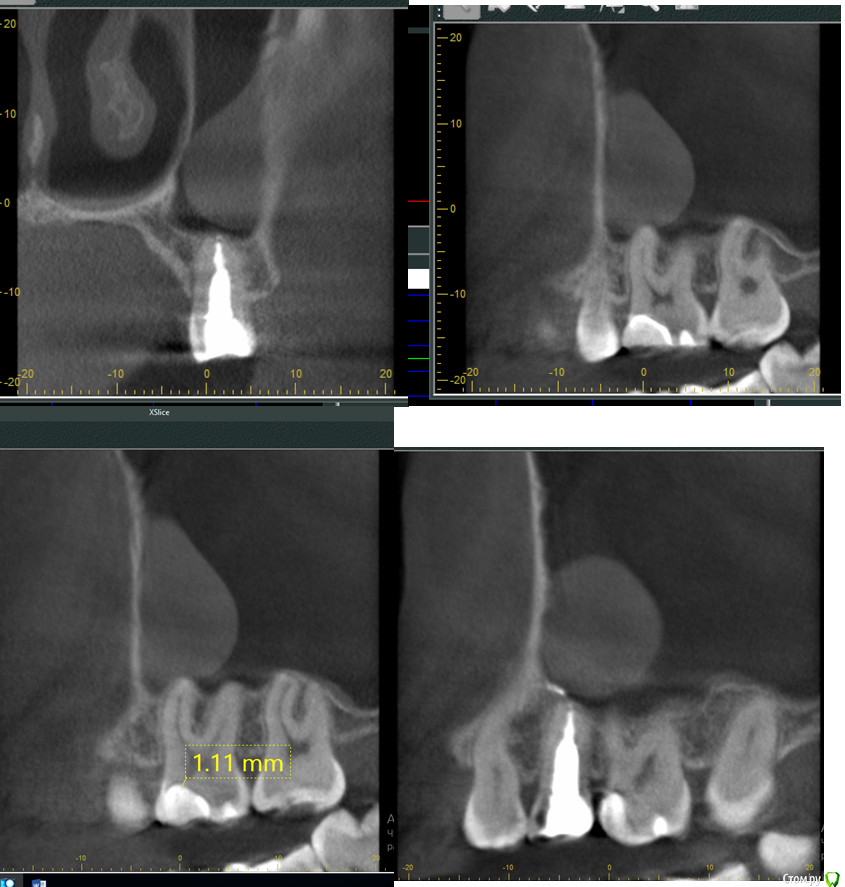

Mashelya Опубликовано 10 марта, 2016 Поделиться Опубликовано 10 марта, 2016 (изменено) Пациентка 27 лет. Жалобы на периодические ноющие боли на вч слева.24- кариес, визуально не глубокий, на медиальной поверхности, на холод не реагирует, 25 лечен эндодонтически год назад, перкуссия безболезненная. 26- пломба. Перкуссия 24- положительная. Отправила на КТ сегмента. КТ показало, что кариес 24 поверхносный, я не включила его в скрины, дело не в кариесе, но перкуссия 24 положительная. Зуб 26- да, под пломбой есть кариес. 27 интактный, 28 отсутствует. Зуб 25- выведен материал в небольшом количестве. Образование в верхнечелюстной пазухе- похоже на мукоцеле. Мукоцеле- порок развития, так? значит не одонтогенной природы. Может ли это образование само по себе давать симптоматику ноющей боли и положительной перкуссии 24? Куда направить пациентку к ЛОРу или в ЧЛХ?Немножко сложно, не знаю с чего начать. Маленький кариес на 24 понятно вылечу, но кариес и перкуссия явно не связаны. 25- выведен материал за апекс, резекция показана? 26 перелечить, скорее всего эндо, но 26 не беспокоит. Со слов пациентки "не понятно, ноет 24 или 25, но стучать больновато по 24" Изменено 10 марта, 2016 пользователем Mashelya Ссылка на комментарий

ger_berra Опубликовано 11 марта, 2016 Поделиться Опубликовано 11 марта, 2016 (изменено) На КЛКТ ретенционная киста .Она не является пороком развития.Это скопление секрета слизистой оболочки синуса.Симптоматику не дает при таких размерах.Если судить по тем скринам,которые Вы показали, то 25 трогать не надо.Материал выведен-и Бог с ним.Снимок 24 зуба не информативный.Там может быть всё,что угодно, например , функциональная перегрузка,локальный пародонтит.Прикус пациента мы тоже не знаем.Самое главное,пациента резать не надо (я имею ввиду ВЧ синус и 25 резецировать не нужно!!!). Смотрите шире на проблему с 24. Я не знаю,может у пациента на противоположной стороне нет зубов или с антагонистами идёт суперконтакт. Изменено 11 марта, 2016 пользователем ger_berra Ссылка на комментарий

St. Опубликовано 13 марта, 2016 Поделиться Опубликовано 13 марта, 2016 25- выведен материал за апекс, резекция показана? 26 перелечить, скорее всего эндо, но 26 не беспокоит. В 25 если опираться только на КТ резекция не показана.По поводу 26 - необязательно что там эндо будет, КТ не совсем пердназначена для диагностики кариеса. Так что я бы советовала изначально убрать старую пломбу и уже по факту решать.И проверьте холодом на витальность 24 и 26. Ссылка на комментарий